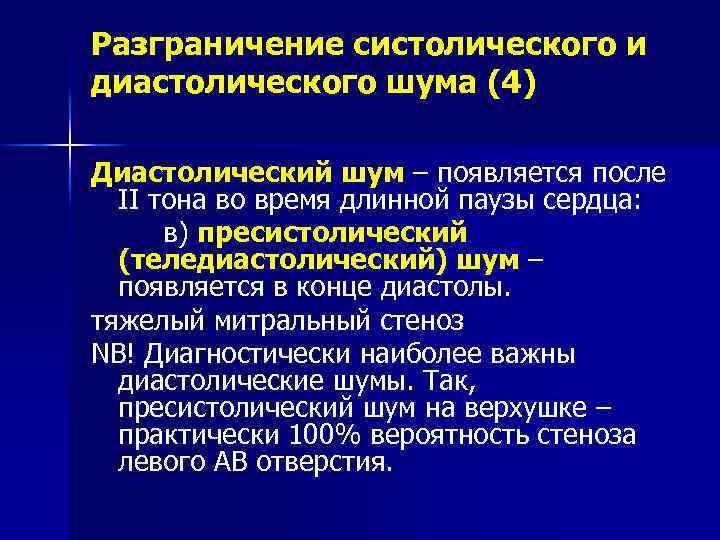

Разграничение систолического и диастолического шума (4) Диастолический шум – появляется после II тона во время длинной паузы сердца: в) пресистолический (теледиастолический) шум – появляется в конце диастолы. тяжелый митральный стеноз NB! Диагностически наиболее важны диастолические шумы. Так, пресистолический шум на верхушке – практически 100% вероятность стеноза левого АВ отверстия.